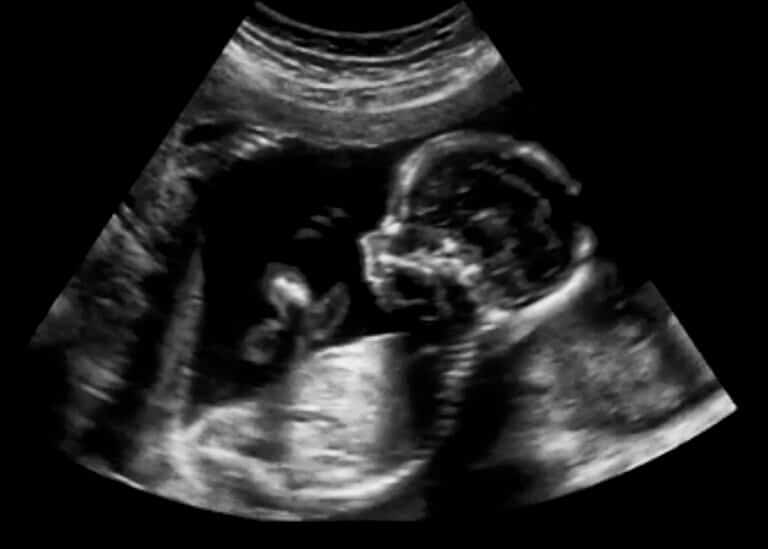

Ultrasound imaging of a four-month-old fetus. Illustration: depositphotos.com

Early signs of autism can be detected already in prenatal ultrasound

This is according to a study at the National Center for Autism and Neurodevelopmental Research at Ben Gurion University